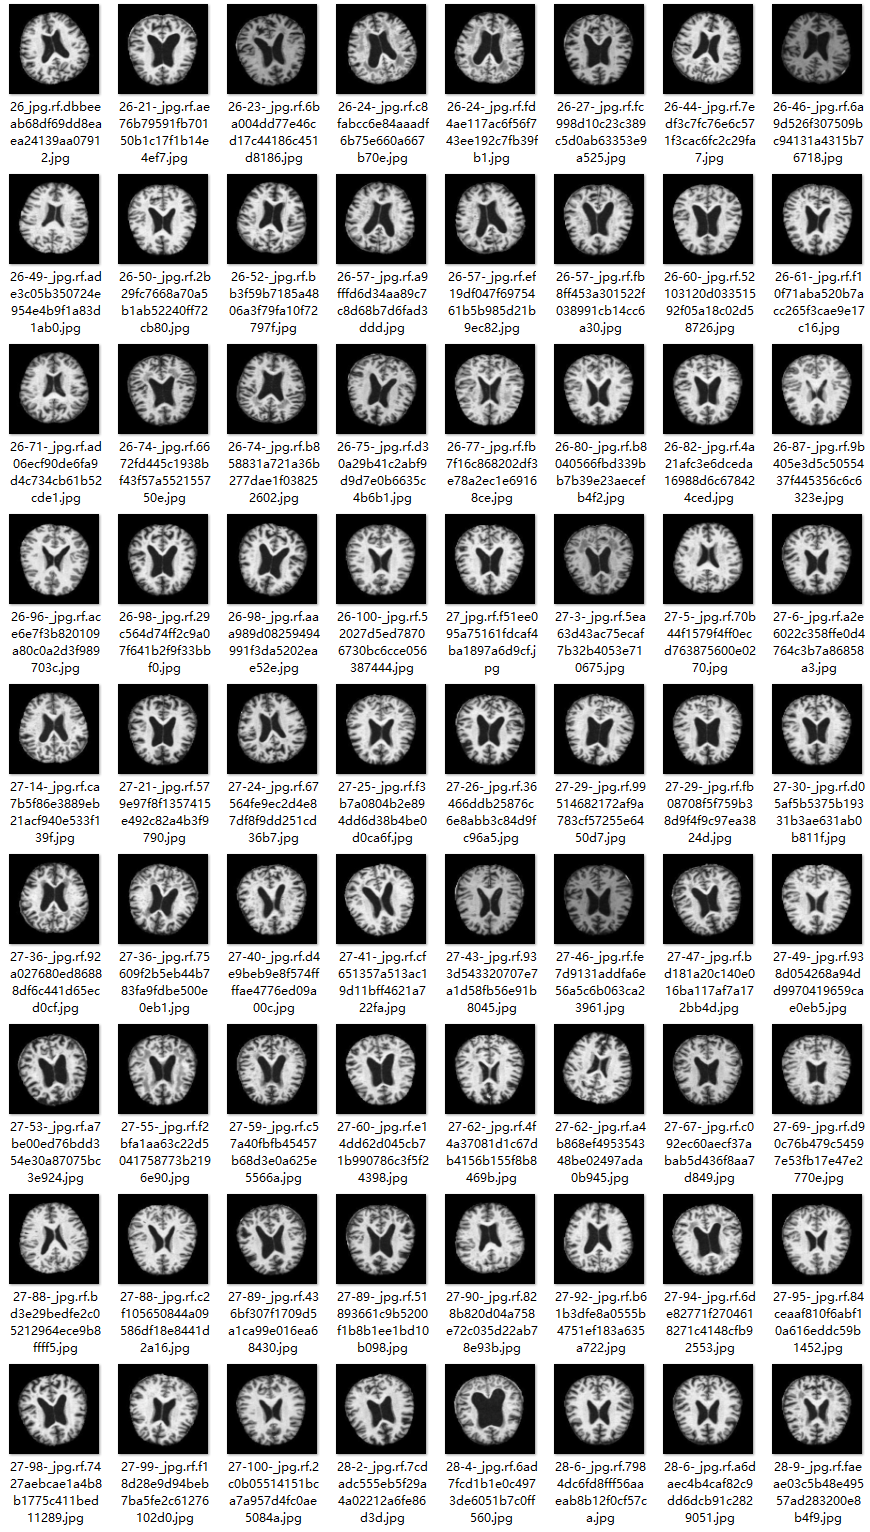

2.数据集准备与训练

本研究使用了包含各种老年痴呆症相关图像的数据集,并通过Labelimg标注工具对每张图像中的目标边框(Bounding Box)及其类别进行标注。然后主要基于YOLOv8n这种模型进行模型的训练,训练完成后对模型在验证集上的表现进行全面的性能评估及对比分析。模型训练和评估流程基本一致,包括:数据集准备、模型训练、模型评估。本次标注的目标类别为老年痴呆症,数据集中共计包含3288张图像,其中训练集占2572张,验证集占716张。部分图像如下图所示:

部分标注如下图所示: